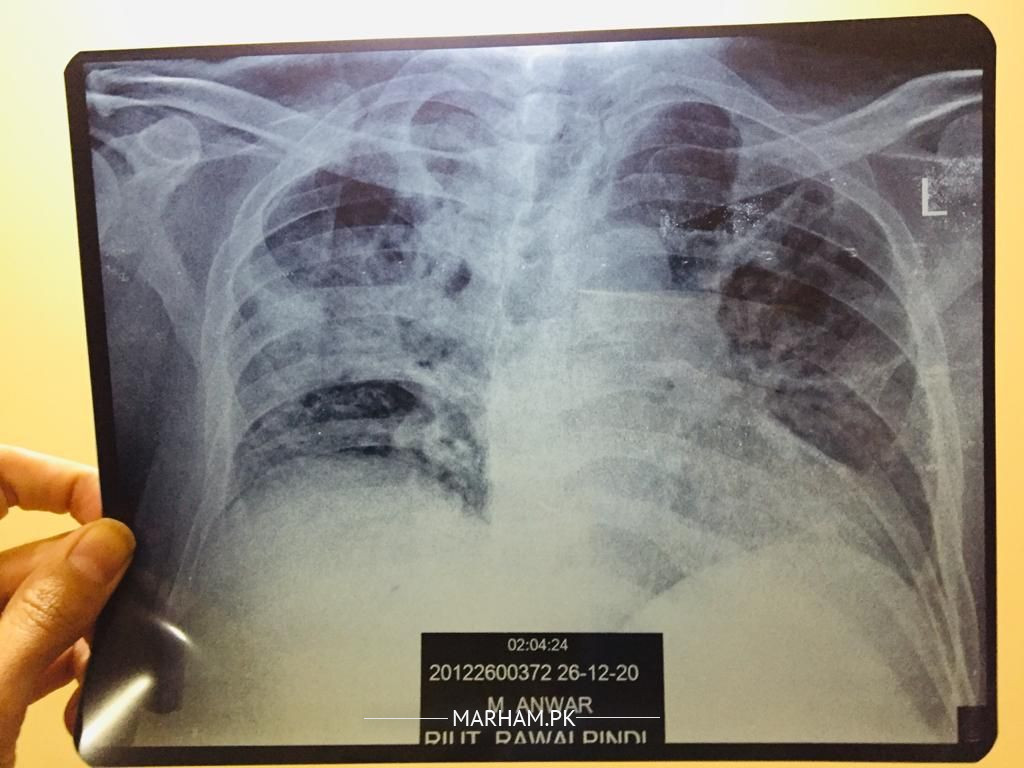

Dear doctors my father is in recovery phase after serious Covid19 today i have done x-ray and ECG of my father just for observe the recovery of inspiration systems re development because from last month he is still on 2ltr oxygen and staying at home with 96/97 sats rate.... Weakness ALHUMDULILLAH recover with good diet and MA SHA ALLAH clinically also very active now so plz doctor give expert opinion on it Medication vibramycine, osnate D, surbux z, loprain, steam 2/3 time in a day pouring and chest physio ongoing good oral intake. If any pulmonologist from rawalpindi Islamabad also pay attention i need your consultation. One x-ray is pervious 26Dec2020 dates mentioned plz review